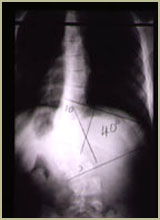

先天性脊柱側凸X線片明顯的脊柱側凸一般體格檢查即可確定診斷,但是對於側凸的角度,仍需要經X線攝片方能最後確定。